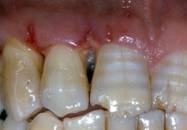

Fig 3

Surgical flap

Int J Med Sci Image

Fig 4

Flap elevation, intra-surgical evaluation of the parameters and surgical curettage of the intra-osseous defect

A full-thickness flap was elevated and the granulation tissue was removed showing the true extension and depth of the infra-bone defect.